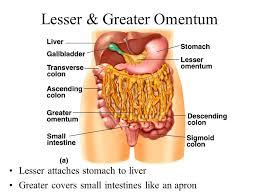

Lesser Omentum

Greater Omentum